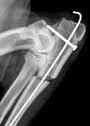

- The surgeries knee during patella dislocations or of cruciate ligament ruptures which have become the first pathologies encountered in canine orthopedics.